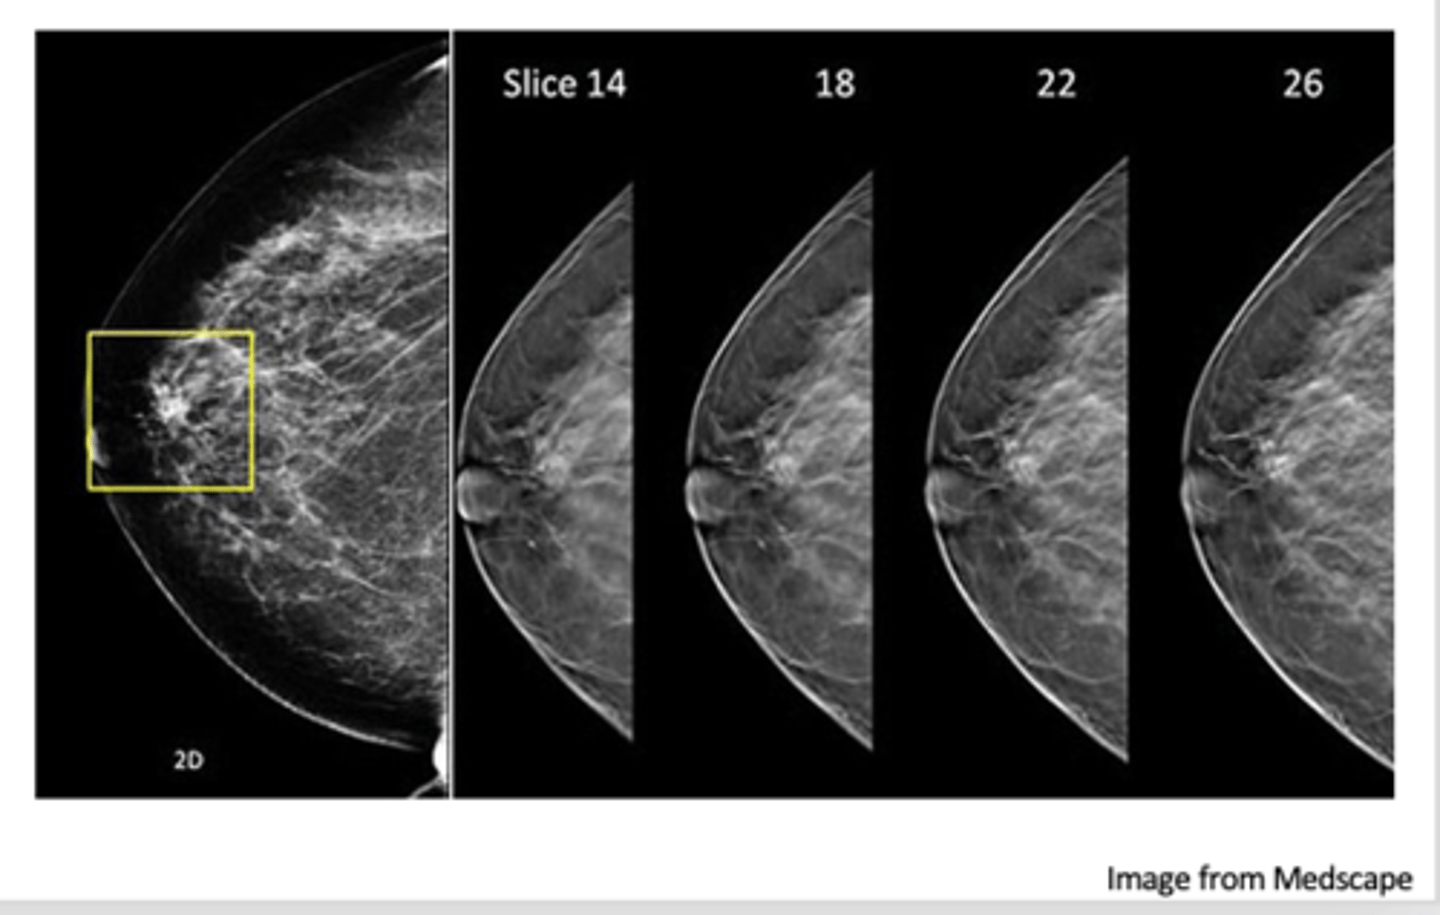

3D Tomosynthesis

addition of 3D technology allows images to be viewed in multiple planes/layers

what is an advantage of 3D tomosynthesis?

Fewer false negative results

Fewer false positive results